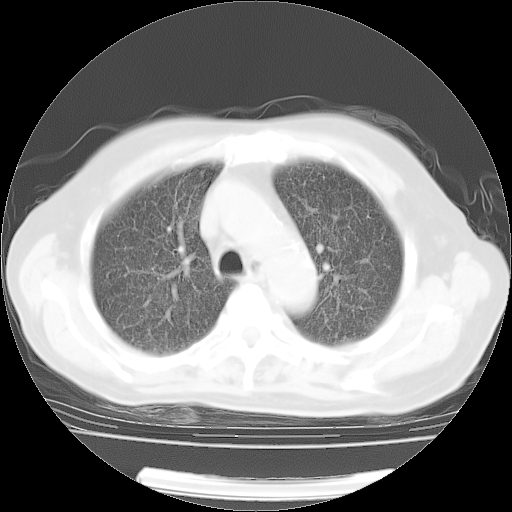

4月14日肺部CT

肺部CT平扫未见异常。